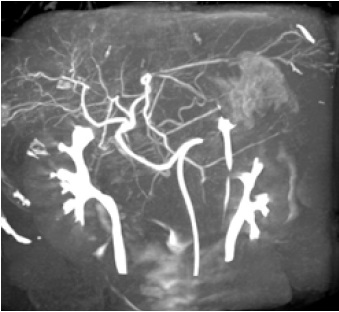

Програмне забезпечення для планування ендоваскулярного стентування аорти (EVAR)

Програмне забезпечення 3D реконструкції

В основу покладена робота в режимі 3D DA або 3D DSA. Зйомку можна виконувати як з операційної, так і з пультової кімнати для зменшення дози на персонал, зі швидкістю обертання С-арки до 50°/с.

Численні режими візуалізації та реконструкції: